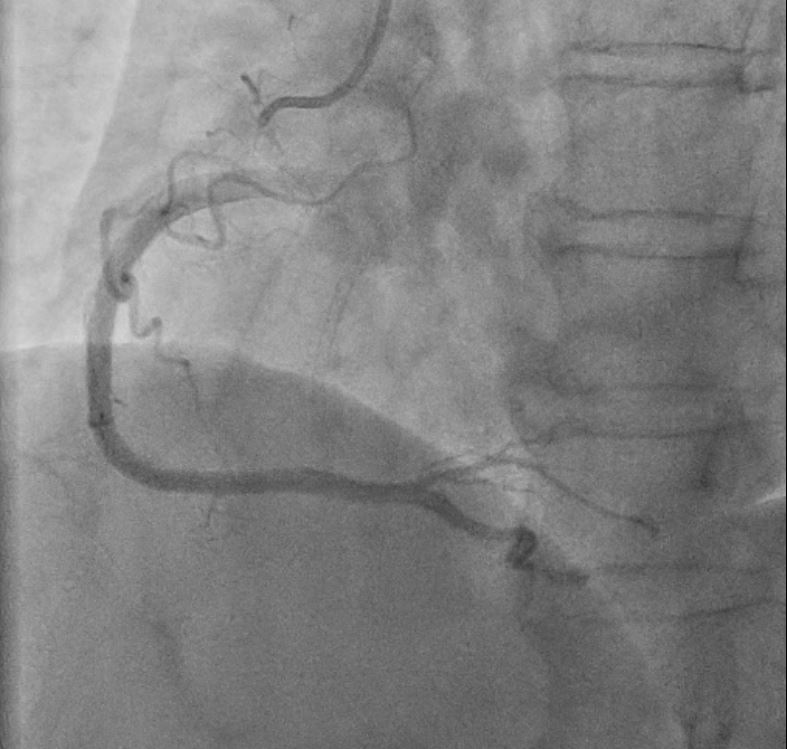

Relevant Catheterization Findings

In the STEMI episode, in Dec, 2022, the LCX and RCA were patent. There were multiple odd stenotic lesions with in mid LAD, with some haziness suggested limited contrast filing. Six days after PCI, there was dissection flap, extending beyond previous angioplasty, with limited flow in LAD, compatible with the unstable ECG changes. In the NSTEMI episode, in Dec, 2022, the LAD was stationary without restenosis. But the RCA for new log lesion at segment 2 to segment 3.

1st PCI for STEMI 1. The odd LAD lesion was checked by IVUS,revealing coronary dissection in mid LAD. 2. Angioplasty was performed with a 2.75*10mm Wolverine cutting balloon up to 8A10¡±, with fair LAD flow. --2nd PCI for recheck and unstable ECG findings 1. For dissection flap extending to distal LAD, wiring with a Sion wire was performed carefully. 2. Check IVUS to confirm true-lumen wiring and the extension of the dissection. Intimal flap and large burden of sub-intimal hematoma were noted. 3. Angioplasty with a 2.0*20mm balloon catheter, but with poor distal flow. 4. Long stenting to mid-to-distal LAD according to IVUS findings, with Onyx 2.0*26mm and Onyx 2.5*30mm 5. Angioplasty with a 1.5*20mm balloon catheter for distal run-off, 4A10¡± 6. Post-stenting dilatation with a 2.5*10mm balloon catheter, 4A10", low pressure considering the sub-intimal hematoma 7. Check final IVUS: The stents were well apposed. The proximal sub-intimal hematoma was not fully covered due to the vessel-size discrepancy. 8. The final flow was fair --3rd PCI for NSTEMI 1. For the un-reasonable rapid progression of the RCA lesion, I checked IVUS and coronary dissection was noted again. 2. No PCI was performed thereafter due to acceptable blood flow. --4th cath half years later The LAD was stationary and the RCA lesion was totally resolved.